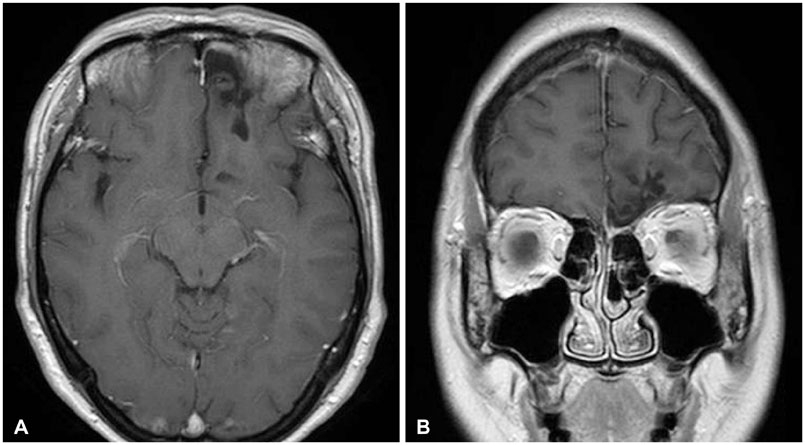

- The olfactory groove schwannoma is a quite rare tumor. We report a case of a 49-year-old woman with an olfactory groove schwannoma attached to the cribriform plate without olfactory dysfunction. She had no specific neurological symptoms other than a headache, and resection of the tumor showed it to be a schwannoma. About 19 months after the operation, a follow-up MRI showed no evidence of tumor recurrence. Surgical resection through subfrontal approach could be one of the curative modality in managing an olfactory groove schwannoma. An olfactory groove schwannoma should be considered in the differential diagnosis of anterior skull base tumors.